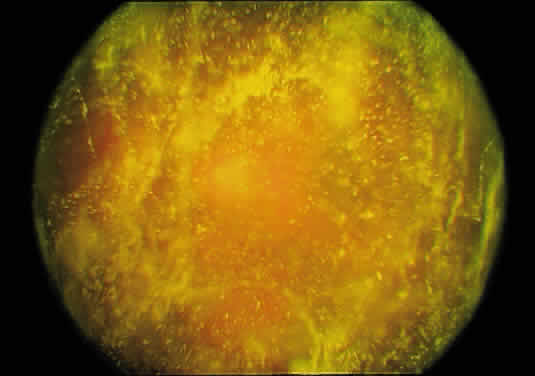

RHEOLOGIC CHANGES

Rheology is a term that refers to the gel–liquid state of the vitreous. After the age of 45 to 50 years, there is a significant decrease in the gel volume and an increase in the liquid volume of human vitreous. Postmortem studies of dissected vitreous qualitatively confirmed these findings and determined that liquefaction begins in the central vitreous.5,12 This finding supports the observation that the central vitreous is where fibers first appear (Fig. 12) and is consistent with the concept that breakdown of the normal collagen-HA association results in the simultaneous formation of liquid vitreous and aggregation of collagen fibrils into bundles of parallel fibrils seen as large fibers.7,8,12 In the posterior vitreous, pockets of liquid vitreous are formed, recognized clinically as lacunae (Fig. 22). When a single large pocket forms, the terms bursa or precortical pocket are used.6,9 As previously mentioned, the large lacuna is a manifestation of age-related liquefaction, or synchisis, and does not represent an anatomic entity.10,11 Flood and Balazs154 found evidence of liquid vitreous after the age of 4 years and observed that by the time the human eye reaches adult size (age 14 to 18 years), 20% of the total vitreous volume consists of liquid vitreous (Fig. 23). In these postmortem studies of fresh unfixed human eyes, it was noted that after the age of 40 years, there is a steady increase in liquid vitreous. This occurs simultaneously with a decrease in gel volume. By the ages of 80 to 90 years, more than half of the vitreous is liquid.

Fig. 22. Human vitreous structure in old age. The central vitreous has thickened, tortuous fibers. The peripheral vitreous has regions devoid of any structure, which contain liquid vitreous. These regions correspond to lacunae, (arrows) as seen clinically with biomicroscopy.